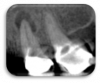

Figure 4. Periapical radiograph of the posterior right maxilla .

Figure 4

Figure 5. Sagittal view of a focused field-of-view CBCT scan on the same patient shown in Figure 4.

Figure 5

Furthermore, 3D imaging identifies up to 40% more of previously undetectable lesions.5 2D imaging modalities provide patchwork information of anatomic segments to represent 3D anatomy. This diagnostic variability is noticeable in endodontically treated and untreated teeth, especially in the posterior maxilla (Figure 4 and Figure 5). Patel et al have also elaborated on the limitations of detecting periapical lesions using periapical radiographs in necrotic teeth.6A visible radiolucency surrounding an apex depends on the size of the lesion, density and thickness of the cortical plate, and the distance between the lesion and cortical plate.